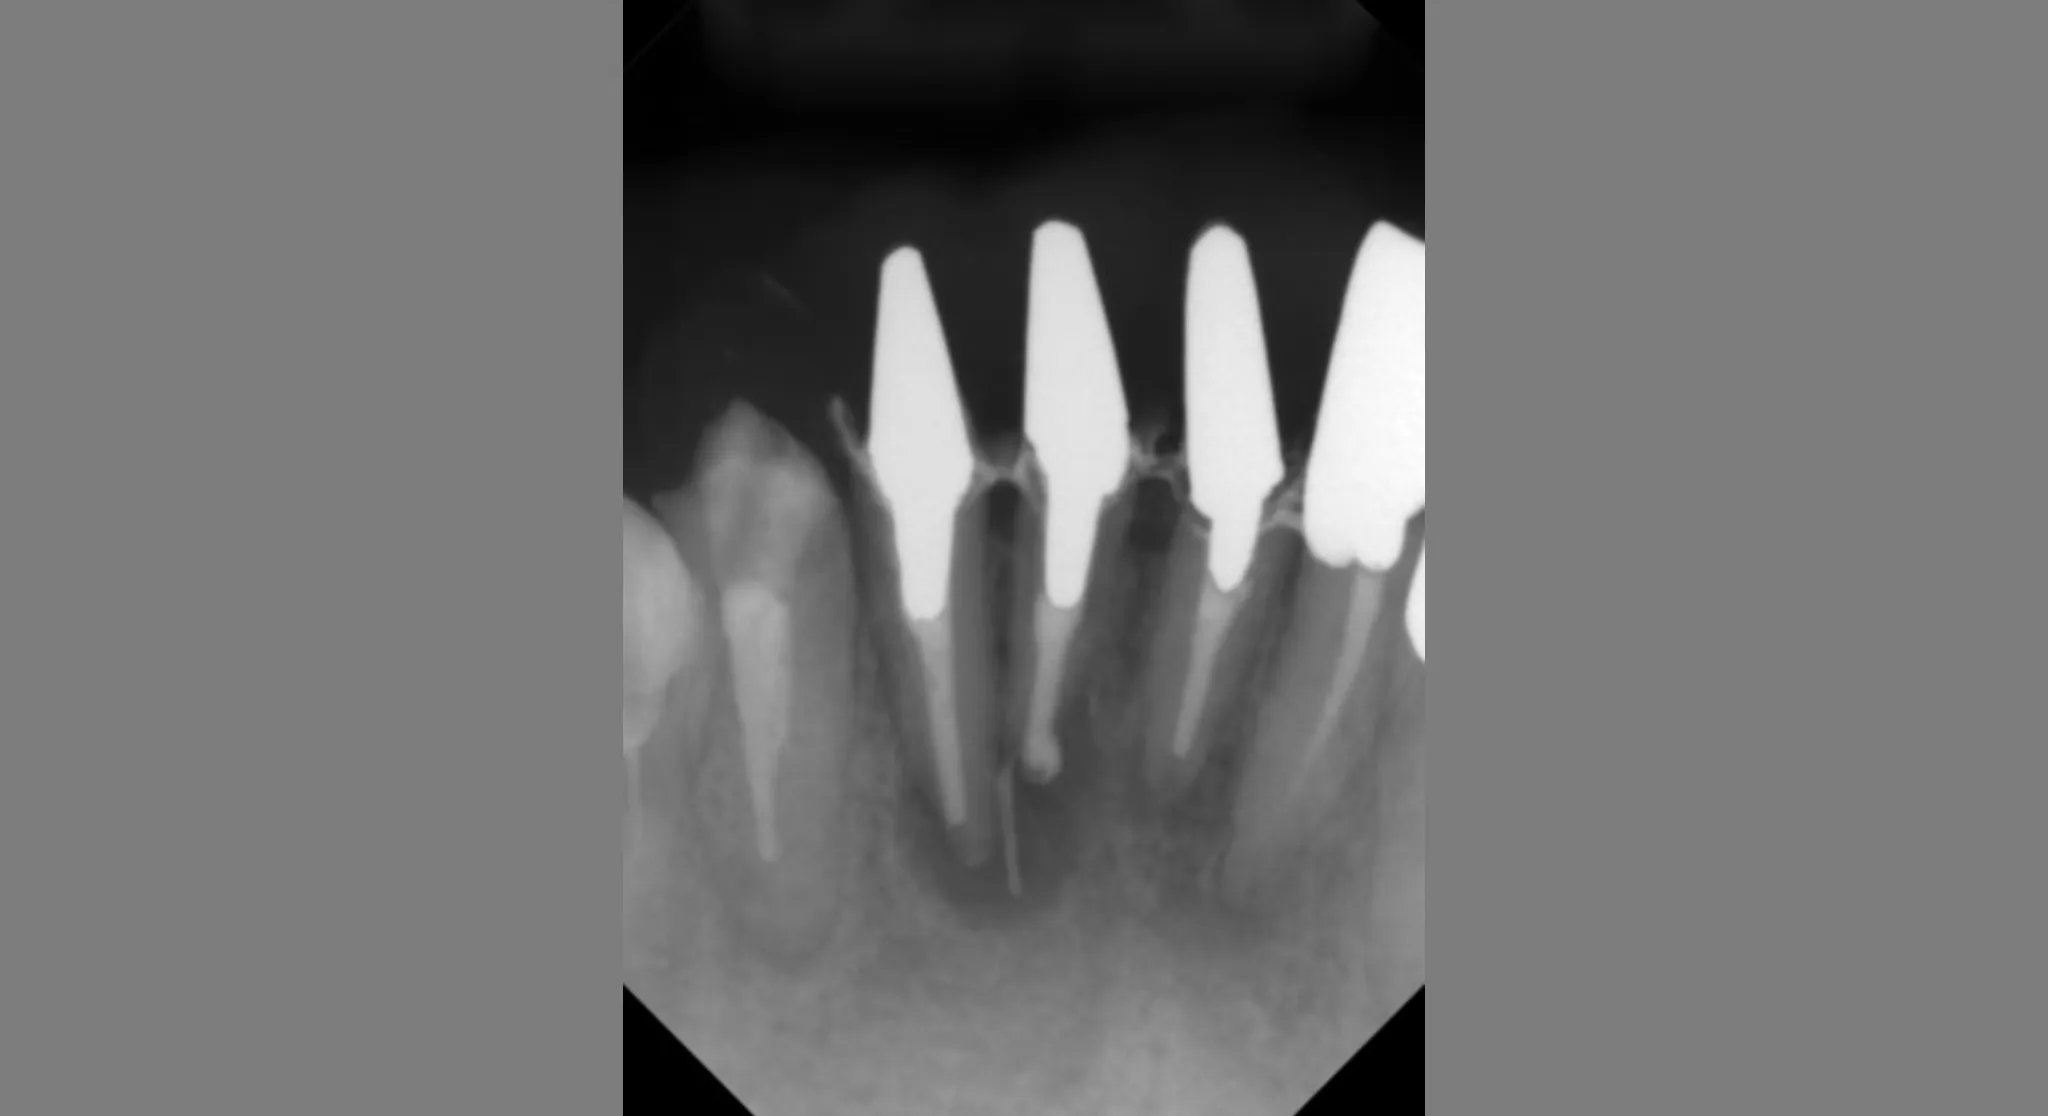

当院では、最新の技術を積極的に導入し、精度の高い治療を提供しています。

特に、すべての治療においてマイクロスコープを導入することで精密な治療を実現します。

最新技術の導入により治療の精度が向上し、再発のリスクを減らすことができるため、患者さんにとっての長期的な健康を守る重要な手段となっています。 -